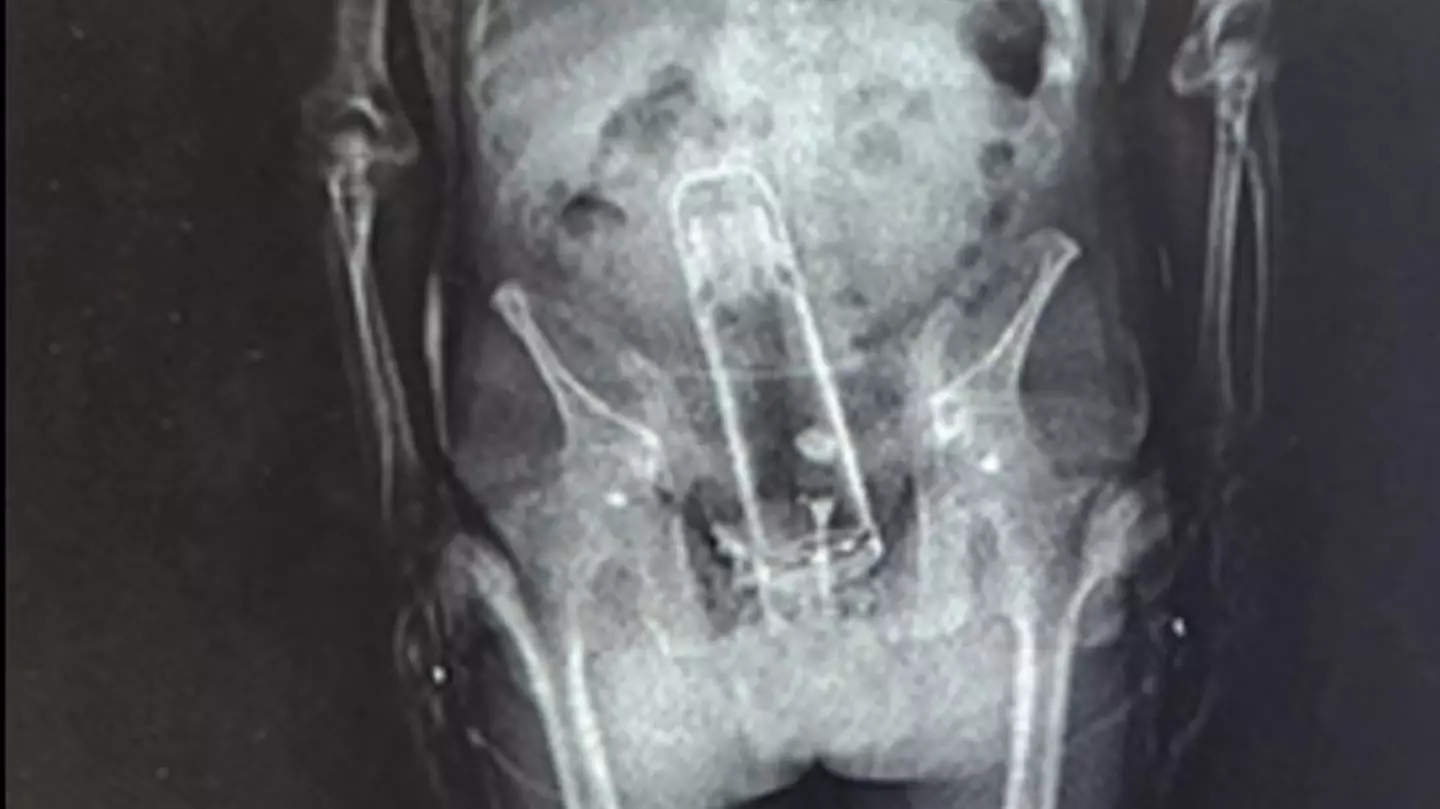

Arrested and taken to jail, the Florida man was put through a customary X-ray scan to detect whether or not he had anything untoward on him,or, in this case, in him.

Officers claimed they'd already found meth on the man when they brought him in, and when they gave him the body scan they saw, well, see for yourself...

That is a Thermos flask lodged firmly up the man's bum, with Sheriff Grady Judge saying: "He brought a thermos into the jail. That’s right.